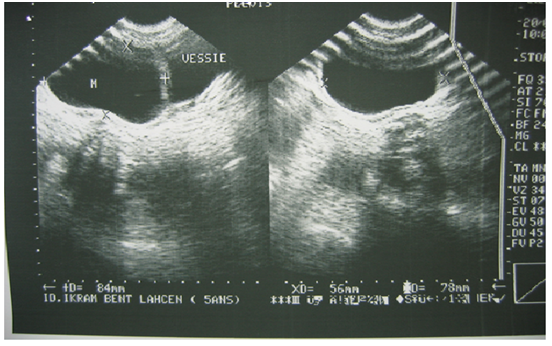

The abdominal ultrasound requested in first intention had mounted a cystic mass, pushing laterally the bladder and could correspond either to a diverticulum of the bladder, or to a cyst of the ovary (Figure 1). CT scan was also performed and had objectified a cystic mass under the umbilical, median compressing behind the bladder dome with overflow to the right of the bladder horn, evoking a cyst of the urachus or an ovarian cyst (Figure 2). Surgical exploration revealed a cystic mass forming part of the bladder dome, evoking a cystic tumor of the urachus. The mass was removed by removing the implantation base from the bladder dome. The postoperative consequences were simple. The pathological report concluded that there was a hydatid cyst of the bladder dome.

Figure 2 CT scan: an umbilical cystic mass, median compressing back the bladder dome.